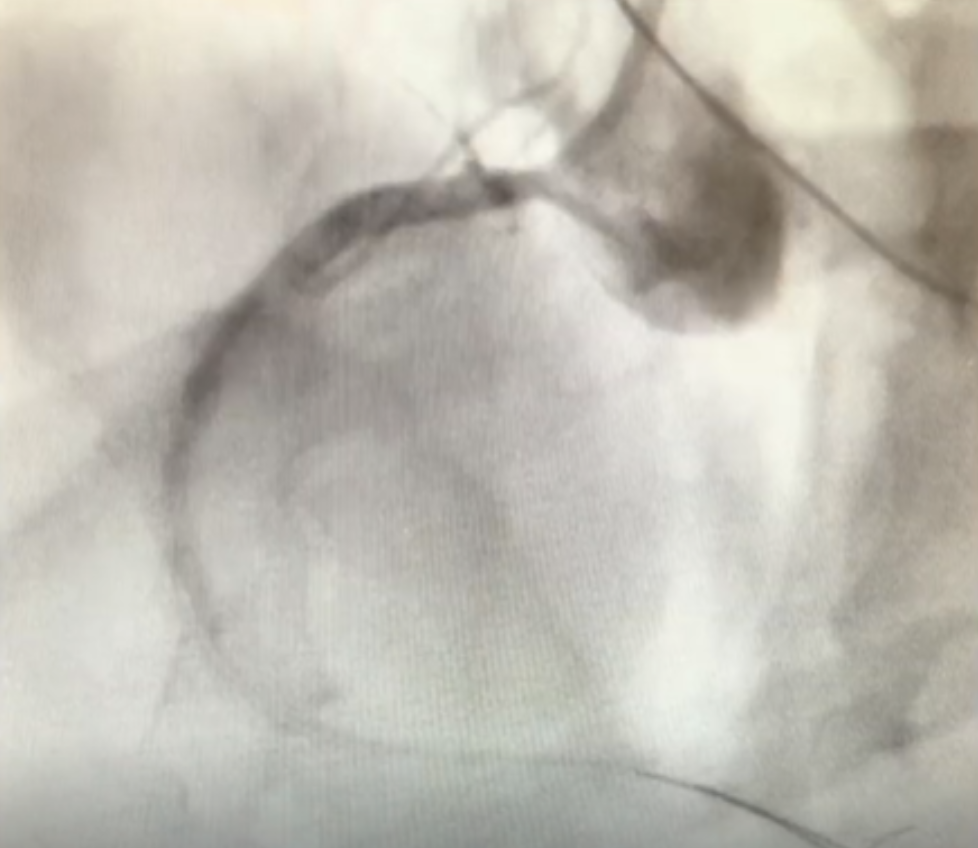

• Inferior ST elevation following balloon valvuloplasty

• Flow remained poor despite multiple thrombectomy catheters and balloon angioplasty

• enVast established excellent flow and allowed successful TAVI procedure